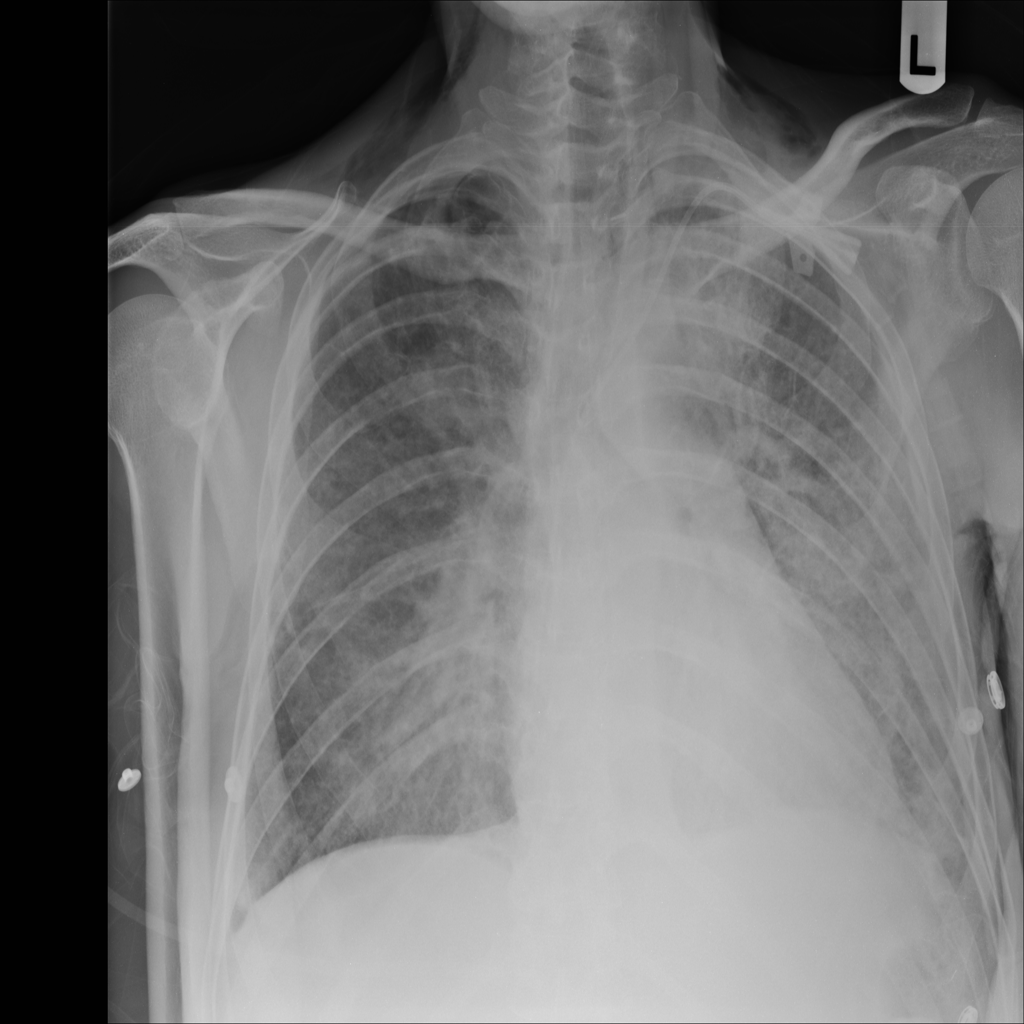

PAT-0E82 · IMG-000Emphysema

PAT-0E82 · IMG-000

AP